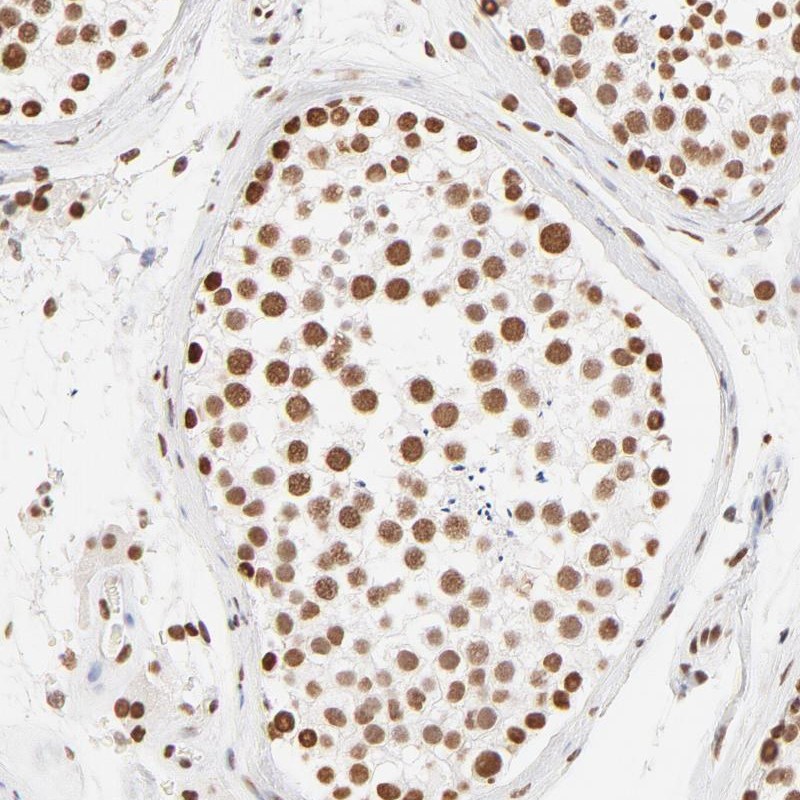

Immunohistochemical staining of human testis shows strong nuclear positivity in cells of seminiferus ducts.